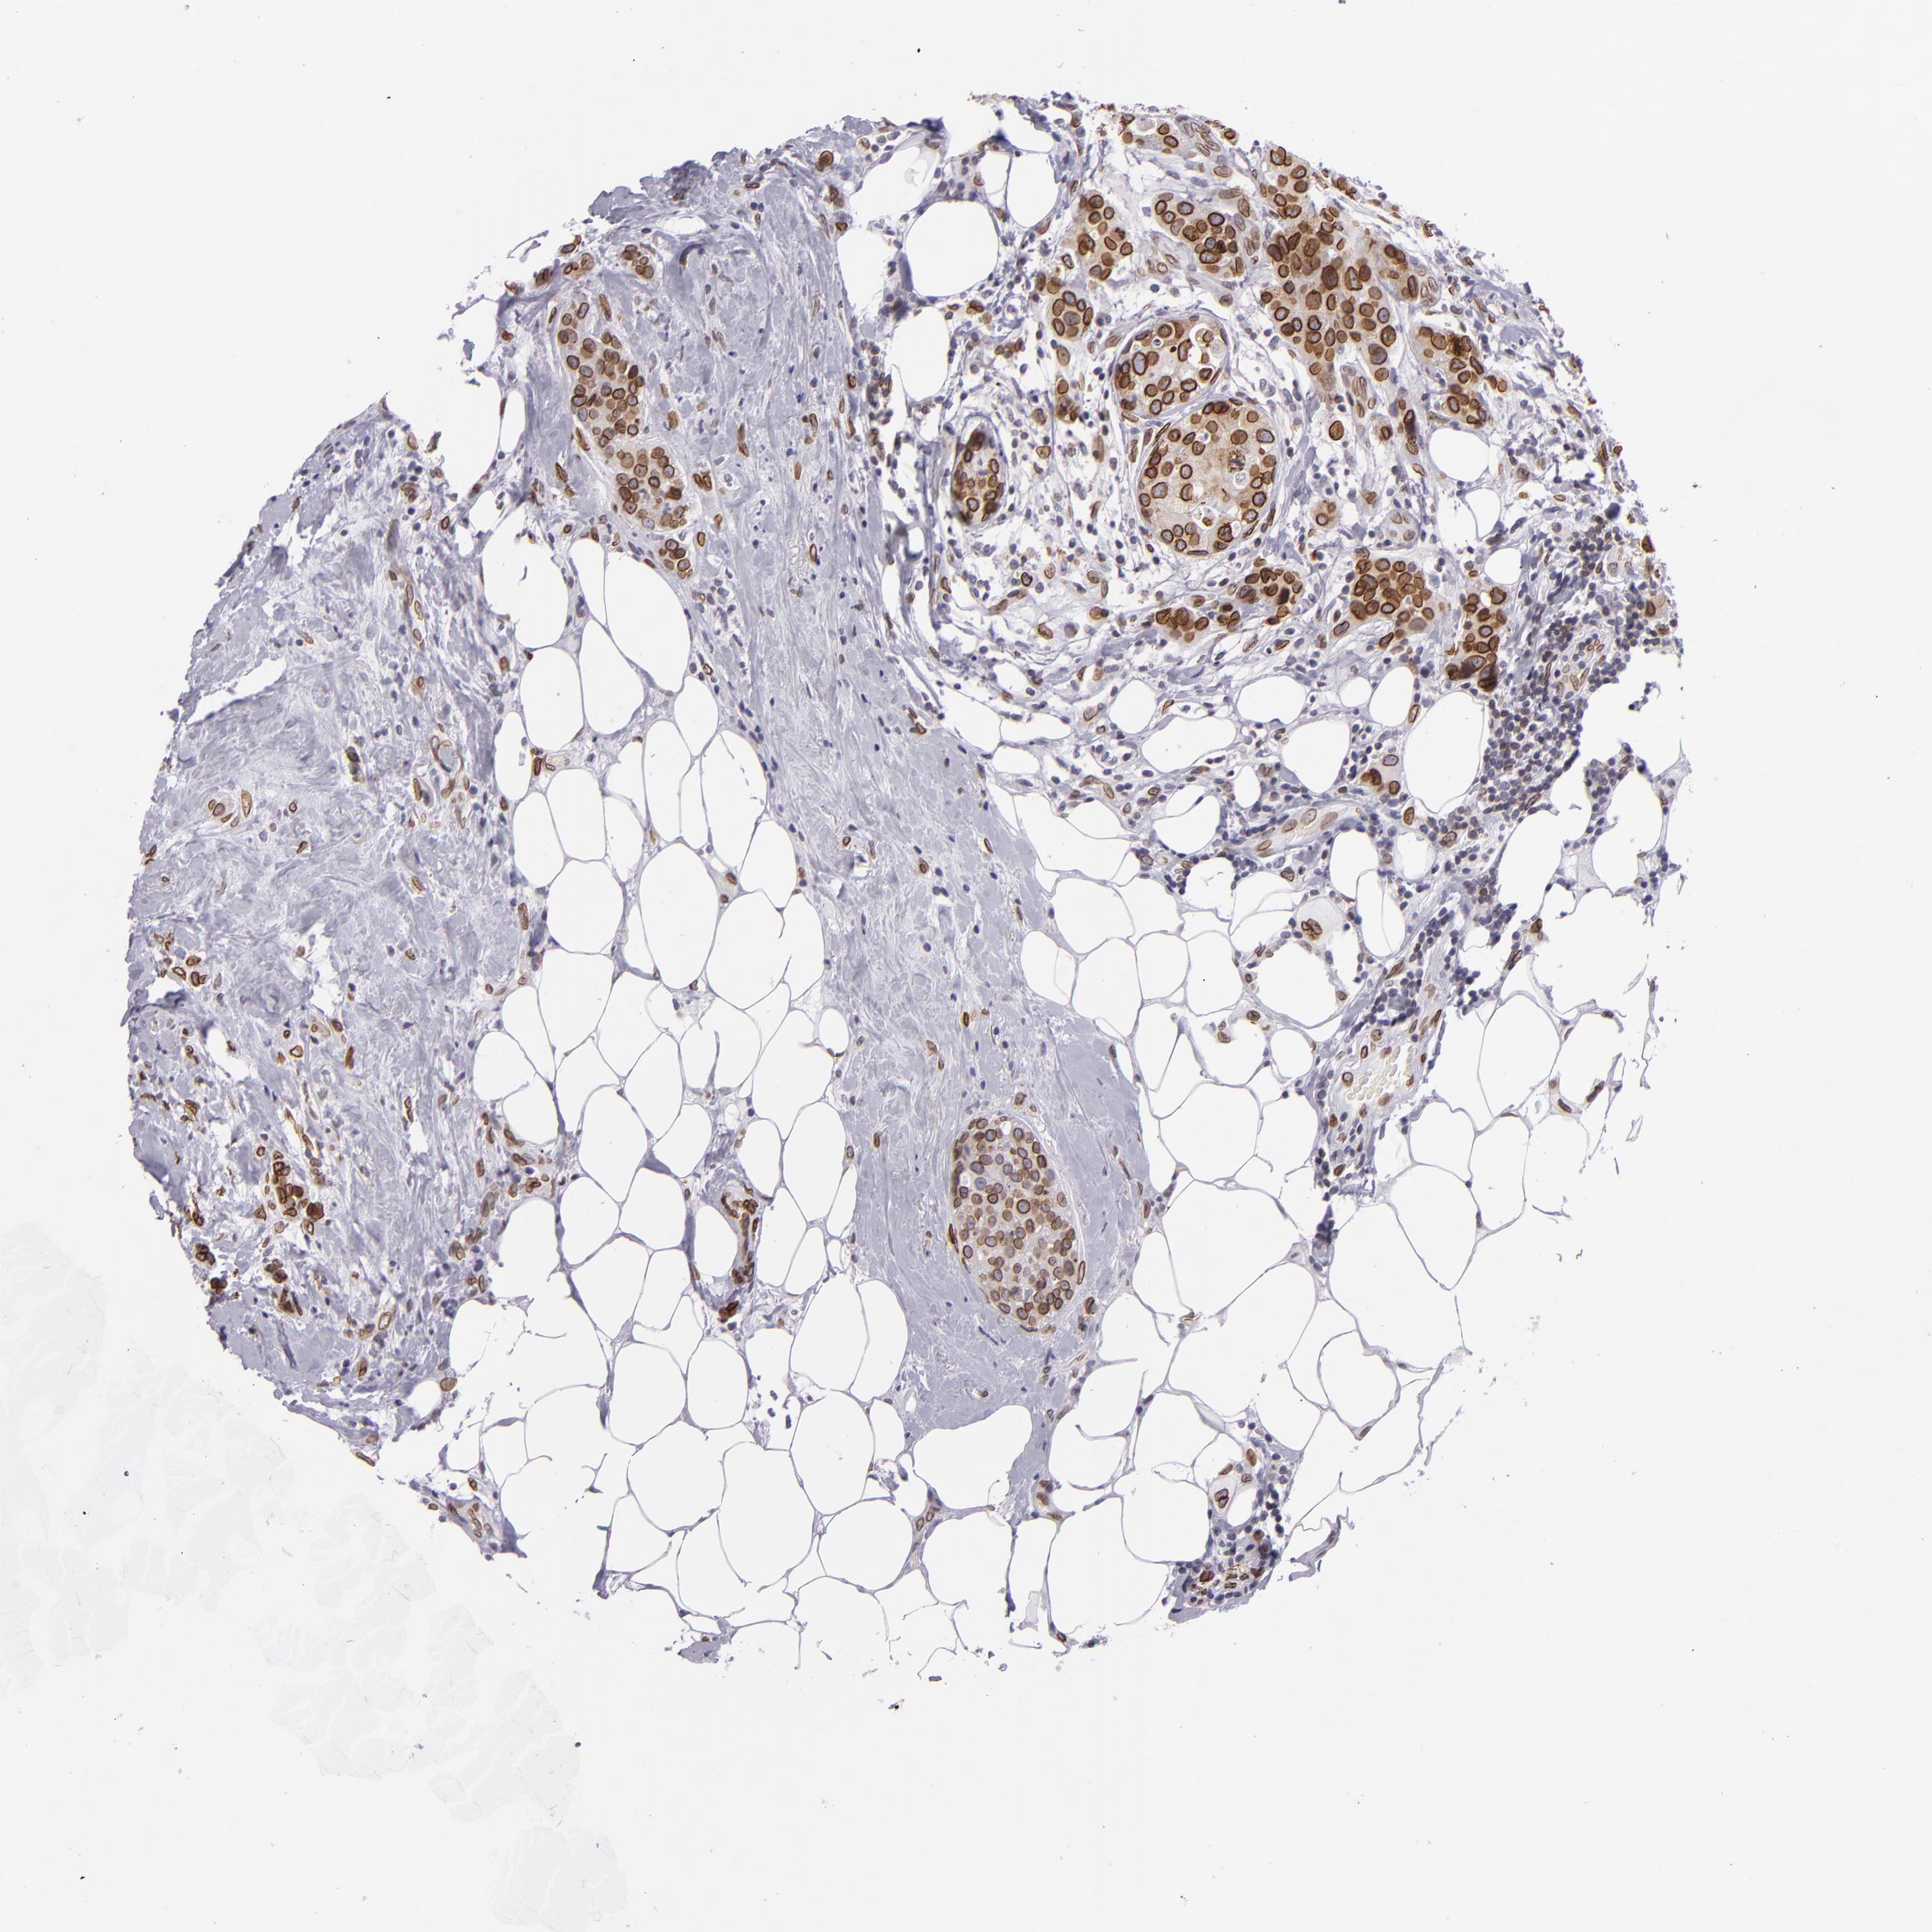

BRCA TCGA BRCA VALIDATION PROTEIN EXPRESSION